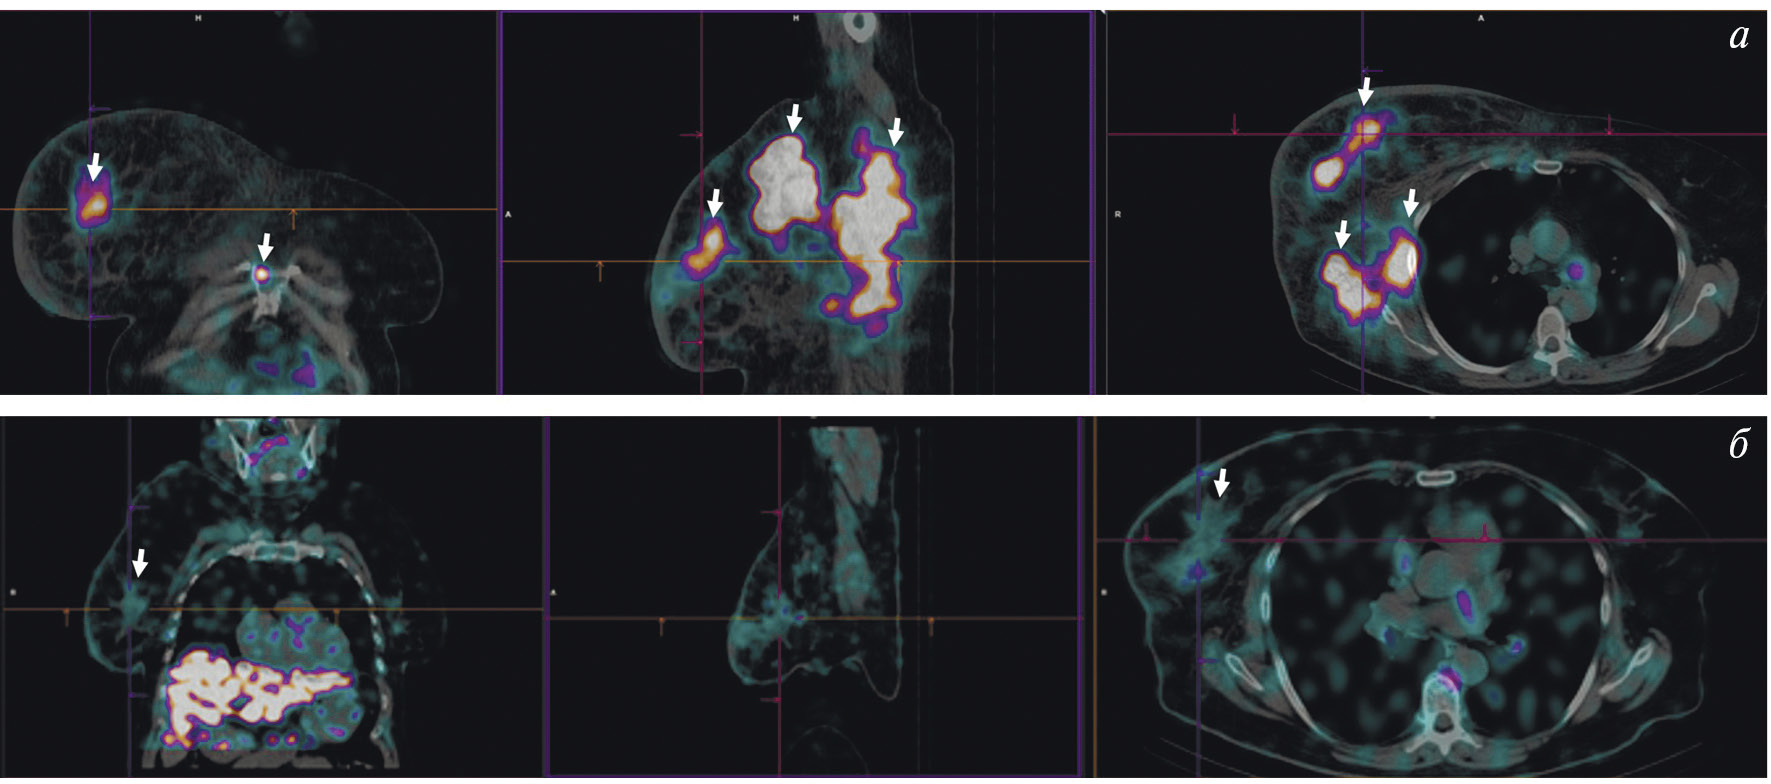

В НИИ онкологии Томского НИМЦ завершены первые фазы клинических исследований нескольких меченных технецием-99м каркасных белков (DARPin, ADAPT, Affibody), обладающих высокой аффинностью к рецептору эпидермального фактора роста второго типа (HER2/neu). Все препараты показали хорошую эффективность определения гиперэкспрессии рецептора HER2/neu при раке молочной железы и стадировании заболевания (рис. 1) [10, 11]. Кроме того, установлена возможность проведения ОФЭКТ/КТ с препаратами на базе скаффолдов для оценки эффекта терапии (рис. 2). Помимо основы РФЛП для диагностики злокачественных новообразований, каркасные белки могут служить вектором доставки при создании таргетных соединений для лечения злокачественных новообразований с гиперэкспрессией рецептора HER2/neu [13].

Рис. 2. ОФЭКТ/КТ-изображение пациентки с HER2/neu-позитивным раком правой молочной железы до начала лечения, выполненное через 2 ч после введения 99mTc-DARPIN-G3 (а), стрелками обозначены первичная опухоль (SUVmax = 3.1), метастазы в лимфатические узлы (SUVmax = 8.8) и кости; ОФЭКТ/КТ-изображение той же пациентки после двух курсов терапии транстузумабом через 2 ч после введения 99mTc-DARPIN-G3 (б), стрелками обозначена первичная опухоль (SUVmax = 0.55), метастазы не визуализируются